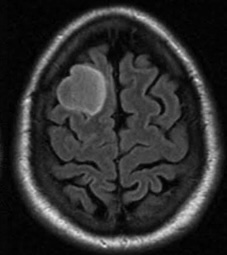

Brain Tumor MRI dataset:

The Brain Tumor MRI Images dataset is a publicly available dataset on Kaggle555https://www.kaggle.com/datasets/sartajbhuvaji/brain-tumor-classification-mri/data. It contains MRI images of human brains divided into four categories: No Tumor, Pituitary Tumor, Benign Tumor, and Malignant Tumor. For our study, we selected three categories: No Tumor (NT), Benign Tumor (BT), and Malignant Tumor (MT). From each category, we chose three MRI images representing different parts of the brain that best illustrate the characteristics of each class. The categories included in this study are described as follows:

The No Tumor (NT) category contains MRI images of healthy brains with no abnormal growths or masses. In these images, the brain tissue appears normal, and there are no signs of tumors or unusual structures. These images serve as a baseline, allowing for effective comparison and detection of abnormalities in other MRI scans.

Refer to caption

(a) NT1

(b) NT2

(c) NT3

(d) BT1

(e) BT2

(f) BT3

(g) MT1

(h) MT2

(i) MT3

Figure 5. Axial and Coronal MRI Images of Brains Representing Different Tumor Categories

The Benign Tumor (BT) category includes MRI images showing non-cancerous tumors in the brain. Benign tumors grow slowly and do not spread to other parts of the brain or body. While generally less dangerous than malignant tumors, they can still cause symptoms if they press on surrounding brain tissue. Accurate identification of benign tumors is important for planning appropriate treatment, which may involve monitoring, minor surgery, or other non-aggressive interventions.

The Malignant Tumor (MT) category consists of MRI images showing cancerous tumors. These tumors are aggressive, can grow rapidly, and may spread to other parts of the brain or body. Malignant tumors require immediate and intensive treatment, such as surgery, chemotherapy, or radiotherapy. Differentiating malignant tumors from benign tumors is crucial, as it directly impacts the treatment strategy and can significantly affect patient outcomes.

Differentiating these categories is essential for early detection, accurate diagnosis, and effective treatment planning. By distinguishing between healthy brains, benign tumors, and malignant tumors, medical professionals can identify abnormalities more reliably, reduce misdiagnoses, and streamline medical care. In this study, we apply our divergence measure to differentiate between the selected MRI images, as illustrated in Figure 5. In Figure 5, the first row shows MRI images from NT patients, the second row shows images from BT patients, and the third row shows images from MT patients.

Using the divergence measure, we calculated estimates for each pair of MRI images and compared the three categories. For calculation, each grayscale image is represented by its pixel intensity values (scaled to [0,1]). These values are flattened into a one dimensional vector and used as the sample data for subsequent analysis. For any two images, denoted data1 and data2, we then computed an empirical based divergence estimate. The resulting values are presented in Tables 4, 5, and 6. A higher value of the divergence estimate indicates a greater likelihood of a tumor. These results demonstrate that the divergence measure can serve as an effective tool for detecting tumors in medical image data.

While our study demonstrates the effectiveness of the divergence measure in differentiating brain MRI images across tumor categories, the results could be further strengthened with longitudinal data, where MRI scans of the same individuals are available at different stages of tumor progression, captured with consistent size and image quality. The current dataset, being cross-sectional, limits the ability to draw more definitive conclusions regarding tumor evolution. Incorporating longitudinal data in future studies would provide deeper insights and allow for more robust validation of the divergence measure in tracking disease progression.